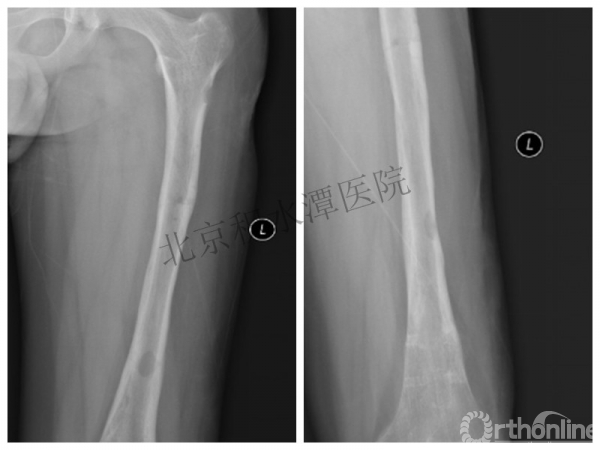

病例分享二

2岁、股骨干骨折,切开+内固定

简单牵引即可!为什么要如此大动干戈?

现实中又是怎样的呢?不知道这属于知识缺乏范畴还是道德品质问题?

匪夷所思!

新生儿股骨干骨折

为什么要手术治疗?

医源性损伤—不愈合!

不具备对儿童骨骼特点的基本了解,不了解儿童骨折的特点,想当然地治疗!

髁上骨折

跨骺板固定

伤后4年